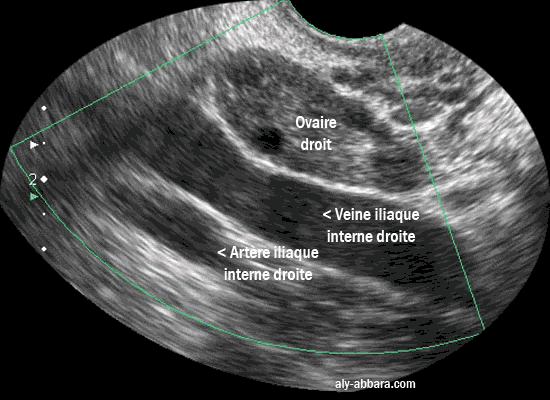

Ovaire droit dans sa fosse ovarique (de Krause)

On remarque la présence de la veine et l'artère iliaques internes droites qui forment la limite postérieure de

la fosse ovarique chez la femme nulligeste.

L'ovaire droit dans sa fosse ovarique, on remarque la présence de la veine et l'artère iliaque internes droites